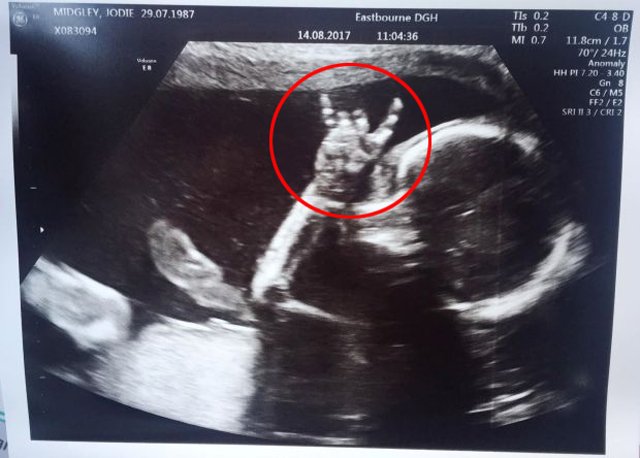

Người mẹ hạnh phúc kể lại rằng vào tuần thai thứ 24, chị đã cùng chồng đi siêu âm để kiểm tra sức khỏe thai nhi. Bác sĩ đã đưa máy siêu âm đi quanh bụng chị Jodie để hai vợ chồng có thể xem toàn bộ cơ thể đứa con. Đó cũng là lúc họ nhận ra một điều vô cùng thú vị ở bàn tay của con gái.

Bé gái giơ tay giống biểu tượng "quẩy lên, vui lên đi".

"Khi bác sĩ siêu âm, con gái tôi đã lấy tay che toàn bộ khuôn mặt, vì vậy tôi đã thử chọc vào bụng mình rồi nói: 'Con có thể chỉ cho bố mẹ biết rằng con vẫn ổn được không?'. Ngay sau lời nói đó, con bé đã đưa tay lên rồi làm hành động hết sức dễ thương", chị Jodie nói. Bé gái trong bụng chị đã giơ hai ngón tay trỏ và út lên giống hệt như biểu tượng "quẩy lên, vui lên đi" mà giới trẻ hiện nay hay sử dụng.

Hành động này của bé gái đã khiến chị Jodie và anh Davie sốc nặng. Ngay cả các bác sĩ cũng bất ngờ trước "thần giao cách cảm" quá đặc biệt của hai mẹ con. "Ngay khi nhìn thấy bàn tay của con, chúng tôi đã nghĩ con là điều tuyệt nhất mà chúng tôi có. Chúng tôi yêu con rất nhiều", chị Jodie chia sẻ.